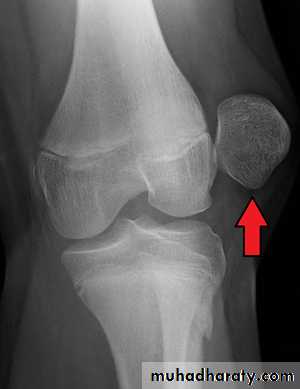

• X-ray

• It shows the displaced patella and the possible associated osteochondral fracture that occurs in 15% of the cases.